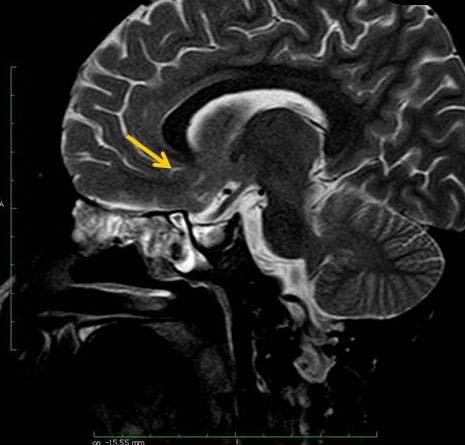

A 12-year-old girl presented with complaints of severe headache associated with vomiting for four days. She also gave a history of reduction in vision (Left>Right) and occasional mild headache of six months’ duration. She had no meningeal signs, fever nor neurological deficit. On examination, she was of short stature and Tanner Stage II [1]. Her ophthalmologic examination revealed a vision of 6/36 in the left eye and 6/6 in the right. Her lateral skull radiograph showed an enlarged sella turcica. Non-contrast enhanced CT showed a cystic lesion measuring 35 x 26 x 22 mm in supra-sellar region with presence of peripheral curvilinear calcification and oedema in left basifrontal region adjacent to cyst [Table/Fig-1]. Contrast enhanced CT revealed a larger peripherally enhancing cystic component in supra-sellar region with mild enhancement of intra-sellar solid component. T1 weighted MR imaging showed hyperintense cyst in supra-sellar location with isointense solid component in sellar location. There was also a hyperintense signal in the brain parenchyma antero-superior to cyst (left basifrontal region) [Table/Fig-2]. T2 weighted MR imaging revealed a well-defined cystic lesion in sellar-suprasellar location with oedema of left basifrontal lobe and adjacent discontinuity in cyst wall due to intra-parenchymal focal rupture of cyst [Table/Fig-3]. Compression and splaying of optic chiasma and optic tracts were also noted. The history, X-Ray, CT and MR imaging findings were suggestive of sellar-suprasellar craniopharyngioma with focal intra-parenchymal rupture of the cyst antero-superiorly into left basifrontal lobe. This rupture of the craniopharyngioma cyst intra-parenchymally causing excruciating headache is the unique presenting feature of this case.

T2WI MR sagittal section showing well defined cystic lesion in sellar-suprasellar location with disruption of cyst wall antero-superiorly associated with mild oedema of left basifrontal lobe (white arrow) due to focal rupture (green arrow) antero-superiorly.